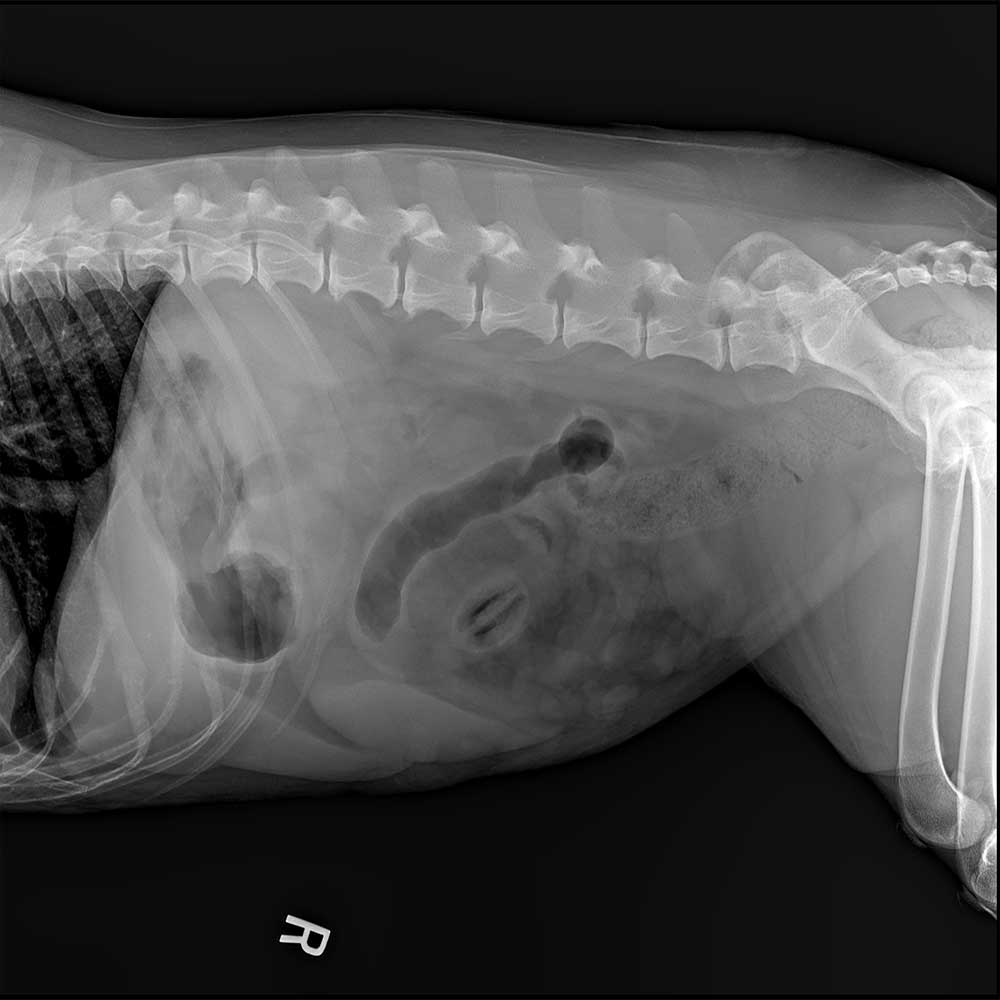

Veterinary radiography (also known as x-rays) provides an in-depth, noninvasive way to image the bones and internal organs of animals. These radiographs help veterinarians diagnose and monitor various conditions, such as bone fractures, dental issues, and internal organ problems.

The process involves positioning the animal and capturing images that can reveal abnormalities

and guide treatment decisions. Veterinary radiography is a critical tool for providing accurate and effective care to animals.